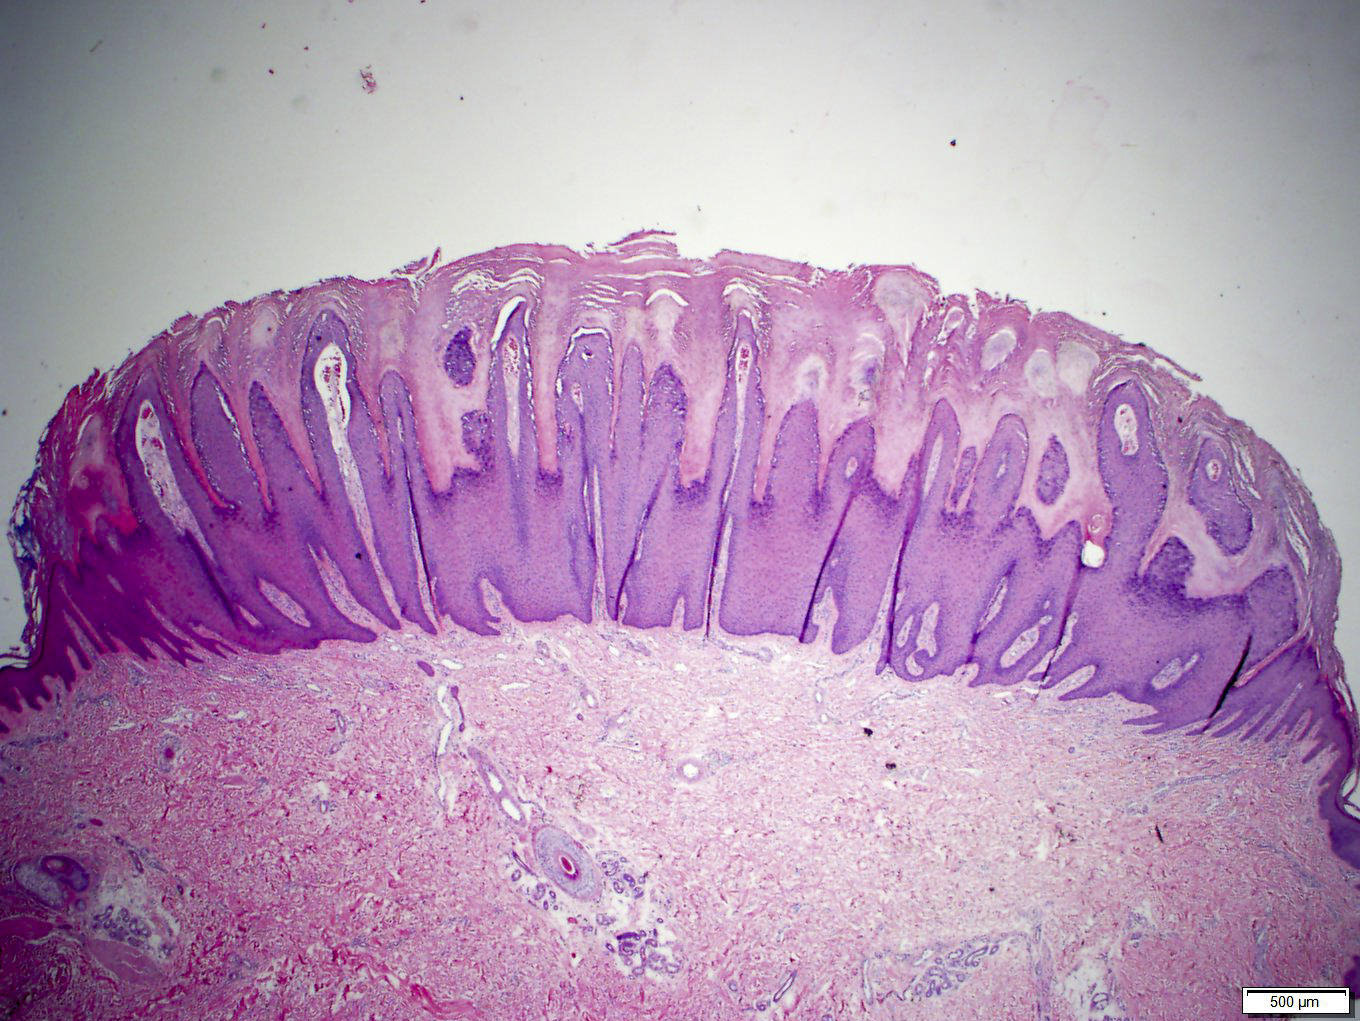

Microscopic (histologic) description

- Common warts (verruca vulgaris) (Arch Pathol Lab Med 2018;142:700):

- Hyperkeratosis, papillomatosis, hypergranulosis

- Columns of parakeratosis, especially over projecting dermal papillae

- Inward bending of rete ridges at borders of lesion (toeing in)

- Dilated capillaries in dermal papillae

- Projects above the plane of the epidermis

- Palmar / plantar warts (verruca palmaris and verruca plantaris) (Arch Pathol Lab Med 2018;142:700):

- Similar to verruca vulgaris (clinical distinction based on location)

- Endophytic growth - greater proportion of the lesion lies beneath the plane of the epidermis

- Condyloma acuminatum (venereal / genital warts) (Head Neck Pathol 2019;13:80):

- More massive acanthosis with bulbous rete ridges (condyloma means fist or knuckle)

Microscopic (histologic) images

Contributed by Heba Ahmed Abdelkader, M.D., Hillary Rose Elwood, M.D., AFIP,

@MirunaPopescu13 on Twitter and @shilpa_rakesh_path on Instagram